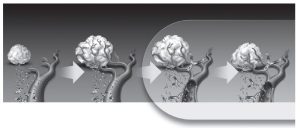

Kolorektaliniam vėžiui gydyti naudojami ir kito tipo monokloniniai antikūnai – angiogenezės inhibitoriai. Jie slopina angiogenezę – procesą, kurio metu išsivysto naviką ir jo metastazes maitinančios kraujagyslės. Dabar žinoma, kad tik susiformavęs navikas, kol neišauga iki 2 mm dydžio, savo kraujotakos neturi. Navikui augant, vėžinėms ląstelėms ima trūkti deguonies bei maisto medžiagų, todėl jos pradeda sekretuoti tam tikras medžiagas -baltymus, vadinamuosius kraujagyslių endotelio augimo faktorius (KEAF). KEAF skatina naujų kraujagyslių, aprūpinančių naviką mitybinėmis medžiagomis ir deguonimi, atsiradimą.

Monokloniniai antikūnai, angiogenezės inhibitoriai, jungiasi prie KEAF ir slopina jo jungimąsi prie specialių receptorių, esančių ant endotelio ląstelių paviršiaus. Neutralizuodamas KEAF aktyvumą, vaistas trukdo susidaryti bei augti naviko kraujagyslėms, drauge slopina ir naviko augimą:

Skiriant šį naują vaistą kartu su chemoterapija metastazavusiam kolorektaliniam vėžiui gydyti, pagerinamas ne tik chemoterapinių vaistų efektyvumas, bet ir prailginama gyvenimo trukmė bei laikas be ligos progresavimo. Naviko ir jo kraujagyslių augimas, KEAF slopinimas ir naviko sumažėjimas vaizduojamas paveikslėlyje.